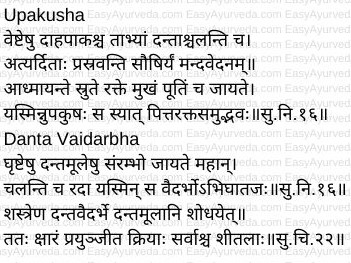

Sanskrit Verses

Ayurveda Understanding of Gingivitis

In Ayurveda the oral and dental diseases are described under mukhagata vyadhis or mukharogas.

A few diseases mentioned in dantamulagata rogas i.e. diseases and afflictions of gums and alveolar processes resemble the description of gingivitis closely.

The symptoms mentioned in gingivitis are scattered along the below mentioned diseases explained in Ayurveda –

- Dantaveshta

- Saushira

- Paridara

- Upakusha

- Danta Vaidarbha

All these conditions appear to be one or the other stage of gingivitis.

Upakusha

This condition is caused by vitiated pitta and rakta (blood).

Symptoms –

- Veshta daha – Burning sensation around the gums

- Veshta Paka – Suppuration around the gums

- Chala Danta – Loosening and shaking of teeth

- Atyarditah prasravanti – bleeds on pressure

- Mandavedana – mild pain

- Adhmayante srute rakte – the gums get swollen up again after bleeding

- Putim – foul smell

Danta Vaidarbha

It is an abhighataja vyadhi – disease of the gums caused by trauma. In this condition redness and swelling occur due to friction / injury to the base of the teeth (gums) and the teeth start shaking.